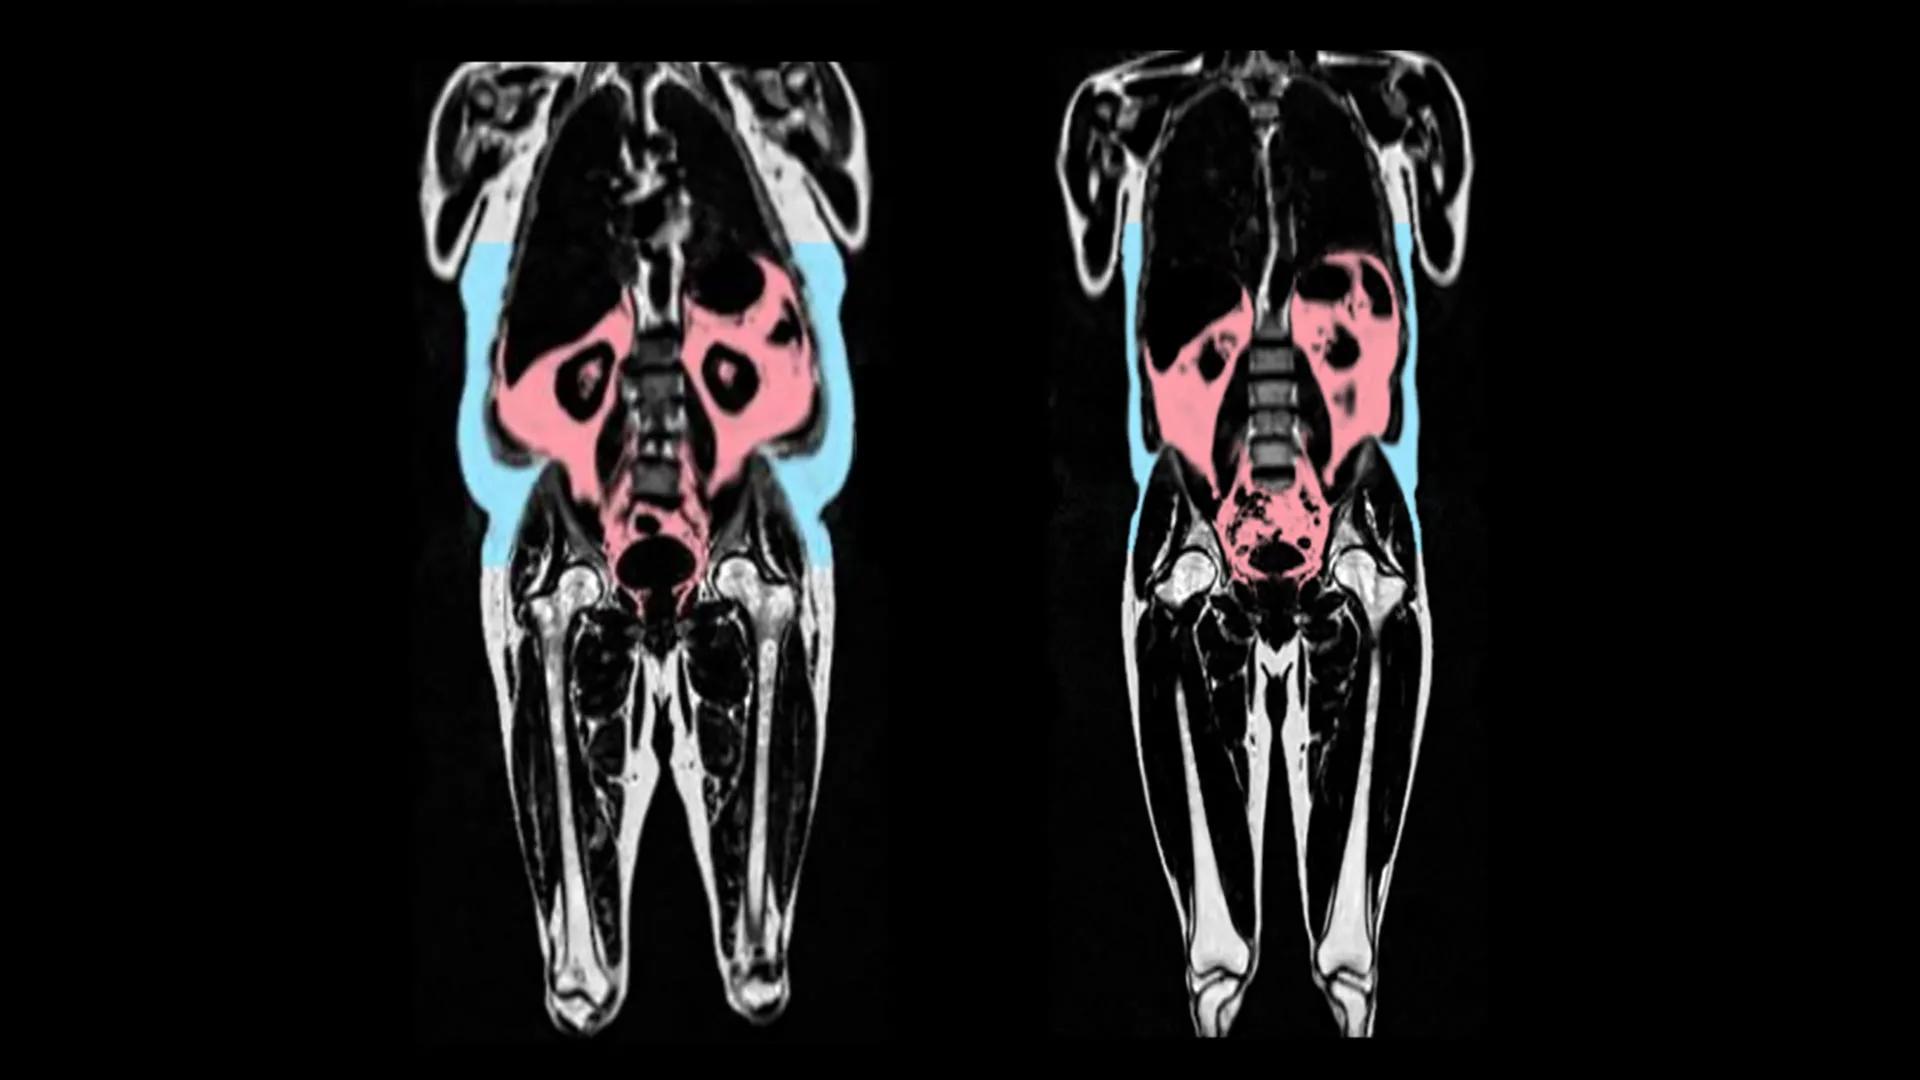

心血管疾病是美国主要的死亡原因之一,每年影响数百万人的生命健康。它涵盖冠状动脉疾病、心力衰竭和中风等多种疾病,而高胆固醇水平是引发心血管疾病的重要风险因素之一。然而,许多尚未被诊断的人群由于未及时接受治疗,导致患心脏病和中风的风险增加。

根据发表在《循环:基因组学与精准医学》(Circulation: Genomic and Precision Medicine)的最新研究,扩大日常筛查范围能够显著改善家族性高胆固醇血症的检测率,从而减少严重健康后果的发生。而调查数据显示,研究团队在参与研究者中发现了419名拥有导致该病的遗传变异者,但其中近75%的人未曾符合现有的临床胆固醇检测或家族病史筛查标准。这一结果凸显了筛查系统中存在的显著差距,阻碍了预防工作的进一步推进。

研究带头人萨马德博士(Dr. Samadder)表示,将遗传筛查整合至日常医疗护理体系是一项迫在眉睫的重要举措。通过早期检测,可让高风险个体更早被发现并接受治疗,从而有效降低心血管疾病的严重后果发生概率。

心血管疾病的高发性和致命性使得家族性高胆固醇血症的筛查问题显得尤为重要。专家强调,扩大筛查范围不仅是一种诊断手段,更是对疾病预防的一次升级。通过精准医学与现代科技的结合,医疗体系可以更加有效地干预此类隐匿性健康威胁,为全球数百万家庭带来健康保障。